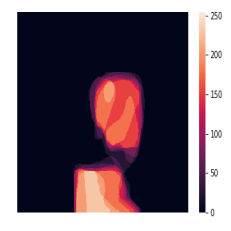

A few sample images and the corresponding masks of the polyp dataset in HyperKvasir are shown in Fig 2. The polyp images are RGB images. The masks of the polyp images are single-channel images with white () for true pixels, which represent polyp regions, and black () for false pixels, which represent clean colon or background regions. In this dataset, there are different sizes of polyps. The distribution of polyp sizes as a percentage of the full image size is presented in the histogram plot in Fig 3, and we can observe that there are more relatively small polyps compared to larger polyps. Additionally, a subset of this dataset was used to prove that the performance of segmentation models trained with small datasets can be improved using our SinGAN-Seg pipeline, and the whole dataset was used to show the effect of using SinGAN-Seg generated synthetic images instead of a large dataset which has enough data to train segmentation models. In this regard, this dataset was used for two purposes:

In total, we have generated synthetic polyp images and the corresponding masks. SinGAN-Seg generates random samples with high variations when the input scale is . This variation can be easily recognized using the standard deviation (SD) and the mean mask images presented in Fig 5. The mean and SD images were calculated by stacking the generated mask images corresponding to the synthetic images related to a real image and calculating pixel-wise std and mean. Bright color in std images and dark color in mean images mean low variance of pixels. In contrast, dark color in std and bright color in mean images reflect high variance in pixel values. By investigating Fig 5, we see that small polyp masks have high variance compared to the large polyp mask as presented in the figure.